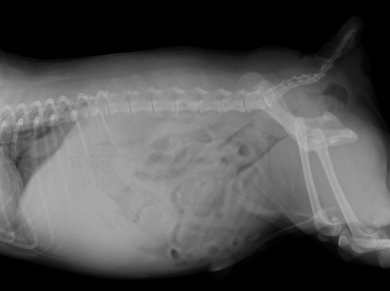

腹部レントゲンにて腹腔内脂肪および肝臓の腫大が認められます。